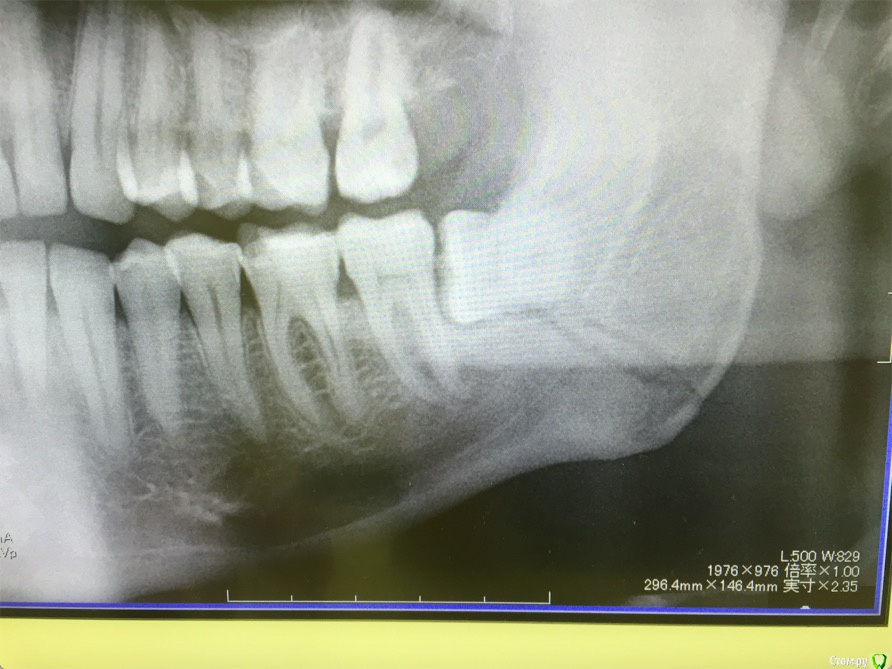

cinovka Опубликовано 10 сентября, 2015 Поделиться Опубликовано 10 сентября, 2015 Здравствуйте. Помогите советом. 15 августа получил перелом нижней челюсти с левой стороны в районе 7-8го зуба.25 числа наложили титановую пластину на место перелома и зашинировали. 3 сентября сняли шины. Разрез делали в ротовой полости и снаружи, для закрутки шурупов.Наружную рану опять вскрыли 1го сентября, т к началось нагноение. Гной выходит постоянно уже 9й день. все болит. зуб мудрости лежит в десне и очень сильно болит.Прошла неделя после снятия шин, а рот также не открылся. максимально открывается на 1-1,2 см.Я нахожусь за границей и врач мой толком ничего не обьясняет.Ответьте пожалуйста на следующие вопросы : 1) Кода пройдет нагноение? И почему оно произошло? (антибиотики, повязки и полоскания постоянные). 2) Когда откроется челюсть? 3) Когда можно будет удалить лежачий зуб мудрости? Снимки номер 1,2,3,4 сделаны до операции 17 августа.Снимки номер 5,6 сделаны сегодня 10 сентября. Заранее спасибо за ответы. Жду с нетерпением. Алексей. Ссылка на комментарий

kriokov Опубликовано 10 сентября, 2015 Поделиться Опубликовано 10 сентября, 2015 1. Зуб надо удалять в ближайшее время, возможно он и пддерживает гноетечение2. Нужен врач челюстно лицевой хирург, чтоб оценить не только снимки но и клинику очно3. Фрагменты челюстей по снимкам в правильном положенииИщите врача 5 Ссылка на комментарий

колесников Опубликовано 10 сентября, 2015 Поделиться Опубликовано 10 сентября, 2015 (изменено) Ошибка в тактике. Зубы находящиеся в линии перелома удаляются.8ки надо срочно удалять. Вопрос с костным фрагментом слева,возможно он секвестрируется. Рот откроется не скоро. И вообще обычно делается межчелюстное шинирование в таком случае на месяц. Антибиотик надо поменять. Обратитесь в стационар. Отделение челюстно лицевой хирургии. Свяжитесь со страховой компанией, если вы заграницей. Изменено 10 сентября, 2015 пользователем колесников 1 1 Ссылка на комментарий

kriokov Опубликовано 10 сентября, 2015 Поделиться Опубликовано 10 сентября, 2015 Вопрос с костным фрагментом слева,возможно он секвестрируется. чего пациента пугать. Там только два фрагмента, большой и малый, две "линии перелома"- это просто обычная картинка , редко когда ломают челюсть как по линейке, равнозначно с вестибулярной и язычной поверхности. Короче-- не секвестр 3 Ссылка на комментарий

ПалСаныч Опубликовано 10 сентября, 2015 Поделиться Опубликовано 10 сентября, 2015 С колесниковым не согласен категорически. Полностью поддерживаю криокова. Это не секвестр, это наложение двух линий перелома с внутренней и наружной стороны. Если б ко мне попал пациент с такой проблемой, то я предложил бы ему такую тактику: 1 пластины снять нафиг, потому чо они там не работают, ибо наложены стнарушением правил остеосинтеза, а так же потому что в ране гной; 2 во время снятия пластин через разрез задренировать рану и провести антибактериальную терапию; 3 наложить опять шины если есть подвижность отломков после снятия пластин. 4 зуб убрать вместе с пластинами. Все написанное ИМХО. 6 1 Ссылка на комментарий

cinovka Опубликовано 11 сентября, 2015 Автор Поделиться Опубликовано 11 сентября, 2015 У Вас остеомиелит челюсти.Если зуб не удалить,перелом не зарастёт никогда.Надо решать этот вопрос незамедлительно.Вы в каком городе находитесь сейчас?Есть ли возможность вернуться в Москву?Вы уверены: что у меня остеомиелит? Врач сказал, что его нет. Предоставление снимки сделаны круговым рентгеном, а не просто с левой стороны. Врач пояснил, что поэтому кажется что там две трещины. Возможно Вы в курсе, извините. Ссылка на комментарий

kriokov Опубликовано 11 сентября, 2015 Поделиться Опубликовано 11 сентября, 2015 1. По Вашим жалобам и клинике тянет на остеомиелит, точно только очно можно2. Вам сделали оптг, аппарат ходил кругом как Вы выразились. При таком снимке, да и при выполнении снимков другими методами линий перелома кажется что две, на самом деле плоскость перелома одна (ПалСаныч выше описал)3.учитывая, что гноетечение и со стороны полости рта в обл 8 и снаружи из послеоперационной раны и отек лица держится выраженный я бы члх еще раз потревожил, не решите на месте, надо возвращаться. Имхо Ссылка на комментарий